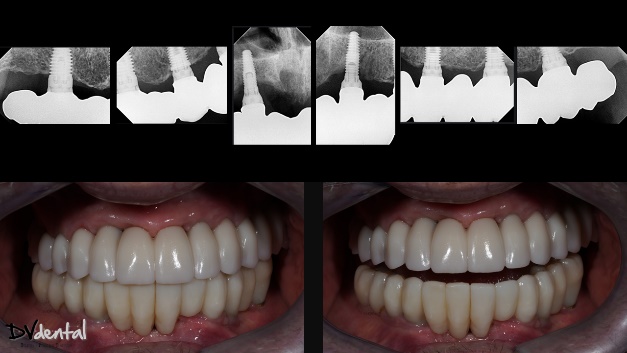

4. Примерка

Перед установкой постоянного протеза пациенту примерили прототип. Это хороший способ оценить эстетику и проверить плотность посадки, в том числе с помощью рентгена. После успешной примерки изготовили и установили постоянный протез (циркониевые коронки на титановой балке). Прицельная рентгенограмма показала, что он сел превосходно, и что внешний вид протеза получился ровно таким, как и планировалось. Пациент остался очень доволен результатом лечения.

Рис. 19,20: Напечатанный прототип протеза для примерки пациентом; проверяется пассивная посадка и прикус.

Рис. 21: Рентген показал хорошую пассивную посадку.

Рис. 22: Интраоральные снимки после лечения (слева: до лечения; справа: после лечения).